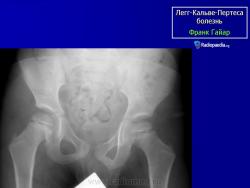

Остеохондропатия головки бедренной кости

(болезнь Легга-Кальве-Пертеса)

(Osteochondropathia caput femoris)

Остеохондропатия головки бедренной кости впервые была описана в 1909-1910 гг. независимо друг от друга Вальденстромом в Швеции, Леггом в США, Кальве во Франции и Пертесом в Германии.

Рентгенологическое обследование помогает в постановке диагноза. Для сравнительного анализа производят рентгеновские снимки обоих тазобедренных суставов, а также рентгенограмму в положении Лауэнштейна. Наиболее полную информацию о локализации и распространенности патологических изменений в головке бедра дает компьютерная и ядерно-магнитно-резонансная томография тазобедренных суставов. В ранней диагностике заболевания высокоэффективно радиоизотопное исследование (сцинтиграфия).

Изменения на рентгенограммах зависят от стадии процесса.

В I стадии (асептиче­ского некроза губчатой кости эпифиза и костного мозга) изменения отсутствуют либо незначительные: в виде остеопороза костей, образующих тазобедренный сустав, извилистости и неравномерности хрящевой эпифизарной пластинки, неоднородности и пятнистости шейки бедра, некоторого расширения щели сустава.

Во II стадии (импрессионного перелома) головка бедренной кости утрачивает характерную трабекулярную структуру, шейка бедра становится более остеопоротичной. Суставная щель отчетливо расширяется по сравнению со здоровым тазобедренным суставом. Эпифиз головки уплотняется, склерозируется и деформируется (вследствие сохраняющейся нагрузки).

В III стадии (фрагментации эпифиза) суставная щель по-прежнему расширена, головка сплющена и как бы разделена на отдельные глыбки или неправильной формы мелкоочаговые фрагменты. Обычно определяется от 2 до 5 таких фрагментов, а иногда и больше. Вертлужная впадина уплощается.

В IV стадии (репарации) определяется формирование новых костных балочек, эпифиз полностью замещается новообразованной костью с участками просветления в центре.

В V стадии (конечной) завершается структурная перестройка и восстановление формы головки и шейки бедра. Суставная щель суживается и приближается по своей величине к нормальной. Если лечение было правильным, форма восстановленной головки незначительно отличается от сферической; в противном случае формируется грибовидная головка с укороченной расширенной шейкой. При этом вертлужная впадина не полностью покрывает увеличенную деформированную головку, что впоследствии приводит к развитию вторичного коксартроза.